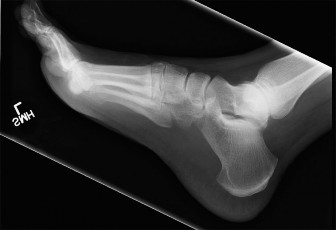

A 54-year-old woman presents to clinic reporting discomfort on the dorsum of her foot with shoewear and pain …

A 16-year-old female sprains her ankle playing lacrosse and is brought to the emergency room. X-rays are nega…

A 60-year-old male presents noting left foot pain of over a year’s duration. He was originally diagnosed with…

A 45-year-old man presents to your office with pain and stiffness in his big toe. He denies any history of tr…